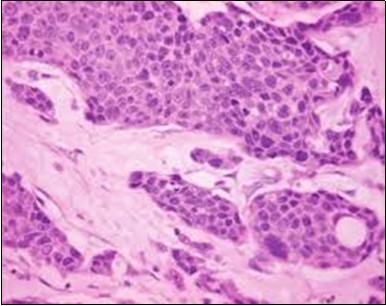

Granular arrangement of malignant cells and intercellular bridges are conspicuous with the demonstration of nuclear atypia, pleomorphism, prominent mitosis and tumour necrosis. A peripheral palisade is discernible within the cellular aggregates. Mitotic figures are common and can be quantified as up to 12 mitosis/ high power field. Tumour differentiation can prominently be of the ductal category with the demonstration of intra-cytoplasmic lumina. Comedo type tumour necrosis is evident along with foci of squamous differentiation The neoplasm is reactive to periodic acid Schiff ‘s (PAS) stain. (Figure 1, Figure 2, Figure 3, Figure 4, Figure 5, Figure 6, Figure 7, Figure 8, Figure 9, Figure 10, Figure 11, Figure 12, Figure 13.

Figure 3.Cohesive accumulations with numerous ductular articulations of carcinoma cells in eccrine porocarcinoma (15).

The neoplasm is composed of lobules of aberrant epithelial cells configured in cords with incrimination of the dermis and epidermis.. Malignant cells congregate within the epidermis or infiltrate the dermis, especially in the primary tumour. Tumour cells within tumour aggregates display a well demarcated cellular outline and appear distinct from encompassing squamous cells. Numerous tumour cell clusters demonstrate a cystic lumen. Prominent epidermal acanthosis is discerned on account of tumour cell proliferation 6, 7.